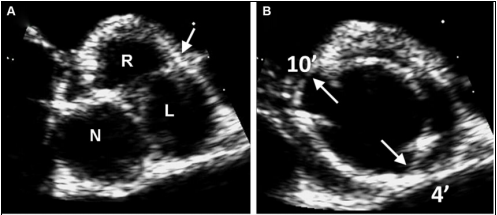

正常主动脉瓣由3个半月瓣组成,称三叶式主动脉瓣(tricuspid aortic valve, TAV),根据瓣膜位置及冠状动脉开口可将其分为左、右和无冠状动脉瓣。而BAV因主动脉瓣发育异常导致相邻两个半月瓣形成融合瓣,部分融合瓣上可见融合嵴,使瓣叶不对称。

Sievers分型

Sievers分型广泛应用于临床,根据融合嵴的数量将BAV分为3型:Type 0型(无嵴)、TypeⅠ型(1个嵴)和TypeⅡ型(2个嵴),其中最常见的是TypeⅠ型,约占90%。根据嵴的空间位置又分为左右冠窦融合型(RL型)、右无冠窦融合型(RN型)、左无冠窦融合型(LN型),其中RL型最常见,约占80%。

最新国际共识认为仅基于外科角度的Sievers分型仍有局限性,因此新的分型为:融合型、双窦型和部分融合型。其中融合型最常见,占90%~95%,相当于TypeⅠ型。双窦型BAV并不常见,占5%~7%,由大小、形状大致相同的两个瓣叶构成,分前侧对侧表型和前后表型(图b)。部分融合型的流行率尚不清楚,表现为典型的三叶瓣膜,但在连合底部可见<50%的瓣尖融合。至于Sievers分型中的Type Ⅱ型,共识认为称单叶瓣较为合适。

融合型

R-L

R-N